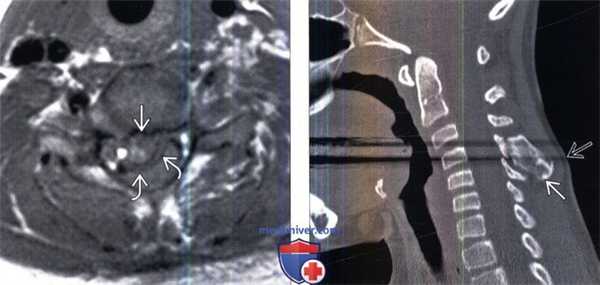

(Слева) Аксиальный срез, Т1-ВИ: костномозговое пространство остеохондромы, расположенное в просвете спинномозгового канала, с преимущественно гипоинтенсивным хрящевым колпачком, вызывающим стеноз шейного отдела позвоночника и сдавление спинного мозга.

(Справа) Сагиттальный КТ-срез шейного отдела позвоночника ребенка: костное образование на ножке исходящее из остистого отростка С4. Образование несколько пролабирует в направлении кожных покровов.